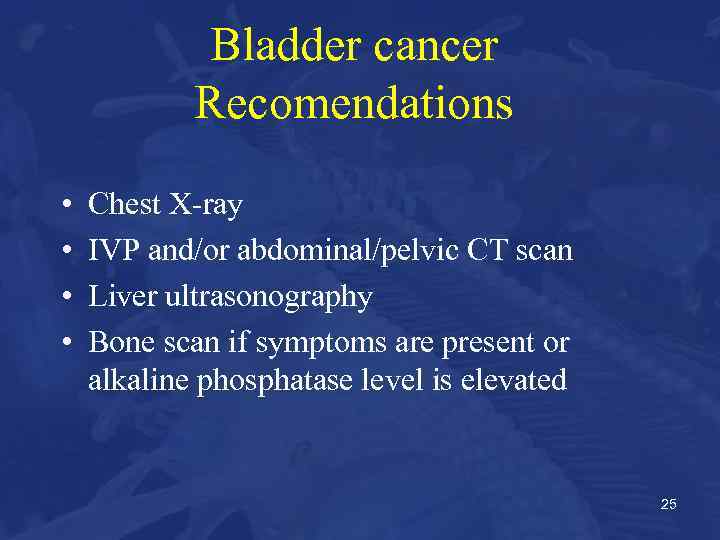

Bladder cancer Recomendations • • Chest X-ray IVP and/or abdominal/pelvic CT scan Liver ultrasonography Bone scan if symptoms are present or alkaline phosphatase level is elevated 25